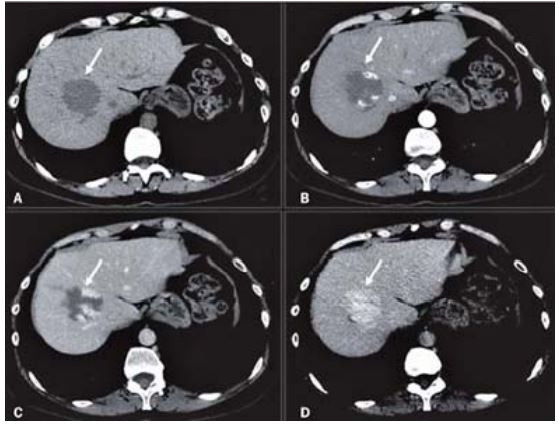

Os cortes abaixo são de uma tomografia computadorizada com contraste para avaliação de uma lesão focal hepática. Analise as imagens e marque a afirmação correta sobre a lesão focal encontrada.